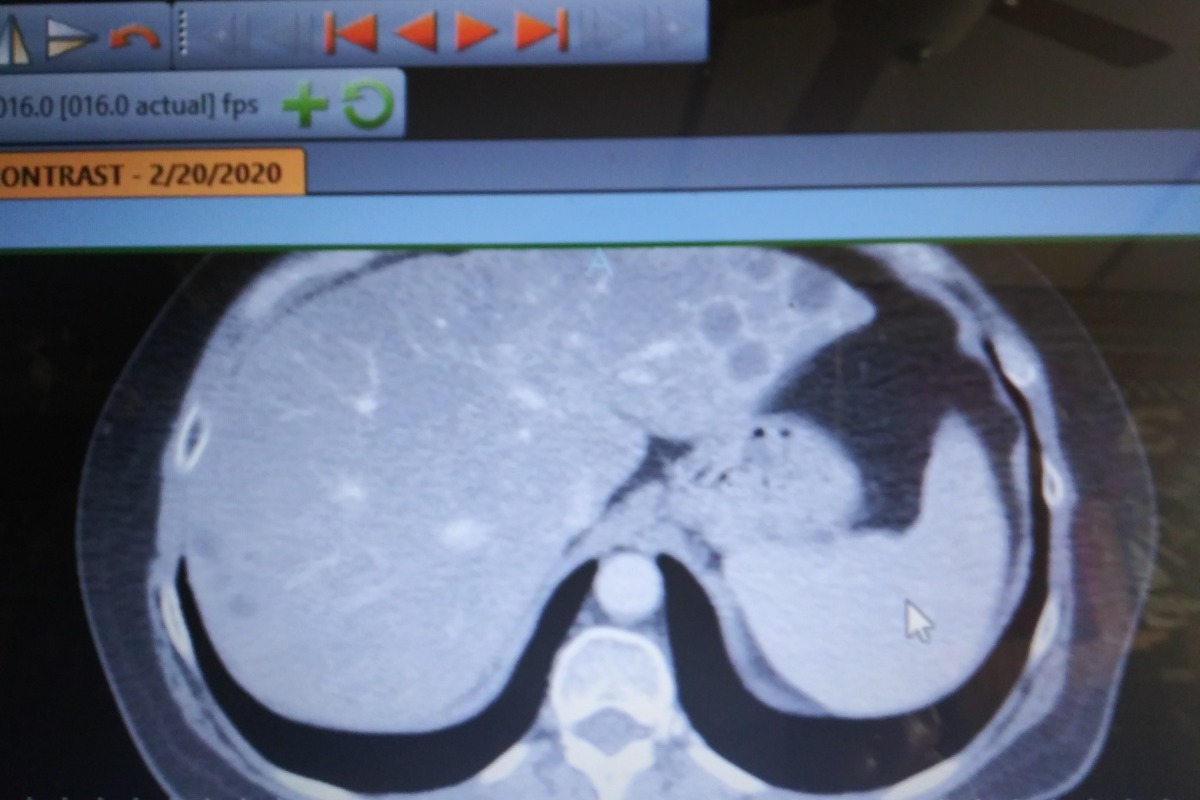

Last February I was diagnosed with Cholangiocarcinoma. This is a rare cancer of the liver bile ducts and will never go away . Abruptly, the company I worked for (AT HOME) decided to terminate me without notice and I lost my health insurance. In order for me to continue my Chemotherapy I have to go through Cobra which is not cheap. Unfortunately my husband just changed jobs and the insurance does not start until May 1st. I do not qualify for anything else so this is my only route. Attached are some pictures from todays CT scan.